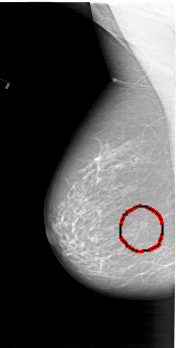

A_1410_1.LEFT_MLO

LEFT_MLO LINES 6256 PIXELS_PER_LINE 3166 BITS_PER_PIXEL 12 RESOLUTION 43.5 OVERLAY

FILE: A_1410_1.LEFT_MLO.OVERLAY

TOTAL_ABNORMALITIES 1

ABNORMALITY 1

LESION_TYPE MASS SHAPE ARCHITECTURAL_DISTORTION MARGINS ILL_DEFINED

ASSESSMENT 4

SUBTLETY 2

PATHOLOGY BENIGN

TOTAL_OUTLINES 1

BOUNDARY